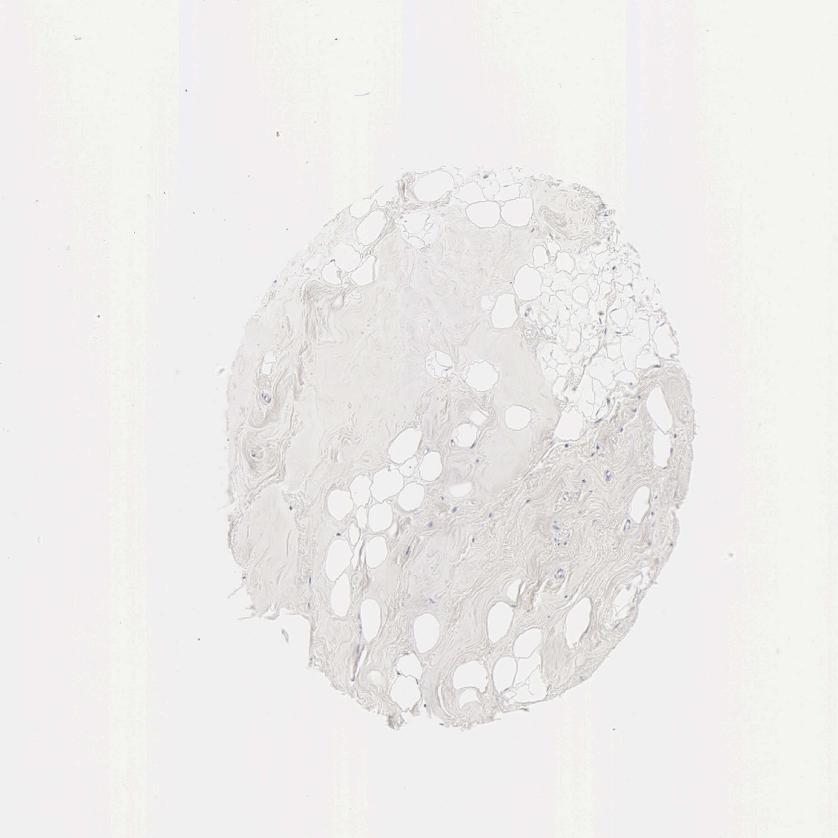

SOFT TISSUE 1 - Antibody stainingi

Antibody staining in the annotated cell types in the current human tissue is reported as not detected, low, medium, or high, based on conventional immunohistochemistry profiling in selected tissues. This score is based on the combination of the staining intensity and fraction of stained cells.

Each image is clickable and will lead to virtual microscopy that enables deeper exploration of all samples and also displays staining intensity scores, fraction scores and subcellular localization as well as patient and tissue information for each sample.

Antibody HPA004335Antibody HPA063916Antibody CAB000071

Chondrocytes -Not detectedNot detected

Fibroblasts Not detectedNot detectedNot detected

Peripheral nerve Not detectedNot detected-